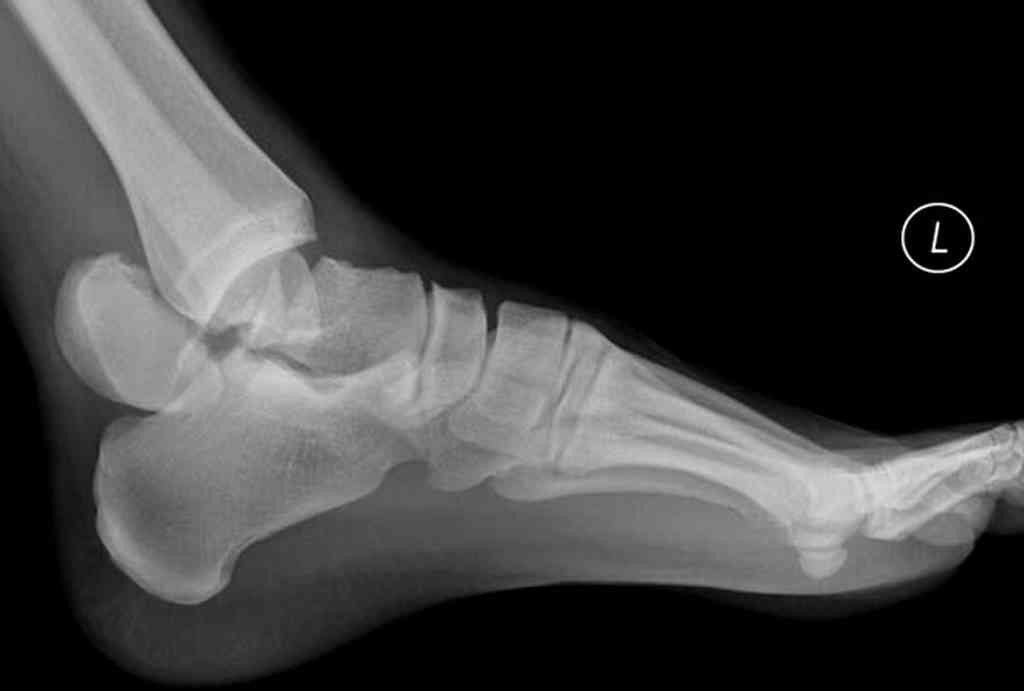

При лечении переломов шейки таранной кости очень важно увидеть вторую проекцию шейки, только боковой проекции недостаточно.

В приложении укладка Канале.